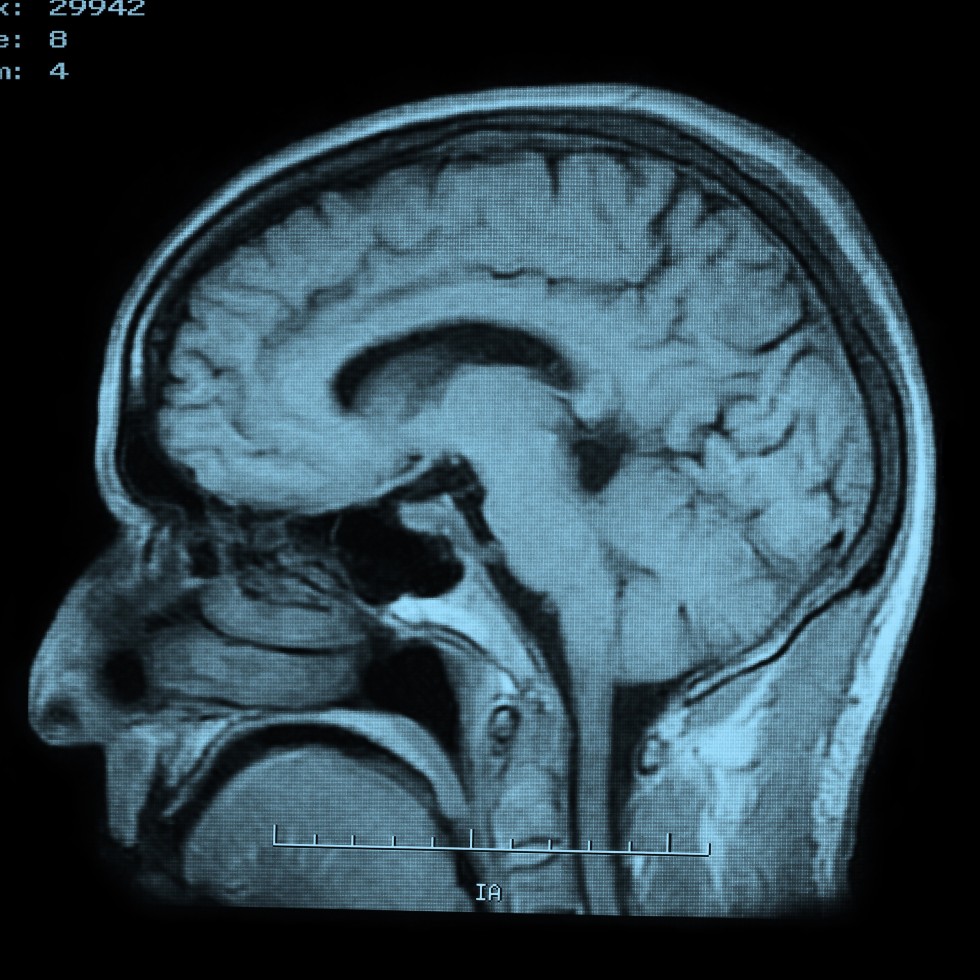

MRI Brain

Magnetic resonance imaging, or MRI, is a method of producing detailed pictures of organs and body tissues by exposing a patient to radio waves in a strong magnetic field. The field is measured and analyzed by a computer, which forms two or three-dimensional images that may be viewed on a TV monitor. Because it uses radio waves and a magnetic field rather than x-rays, there is no exposure to radiation. An MRI of the brain provides high quality two and three-dimensional images that can show both surface and deep brain structures with high clarity and accurate anatomical detail. An MRI is used to detect changes that occur in these structures over time.